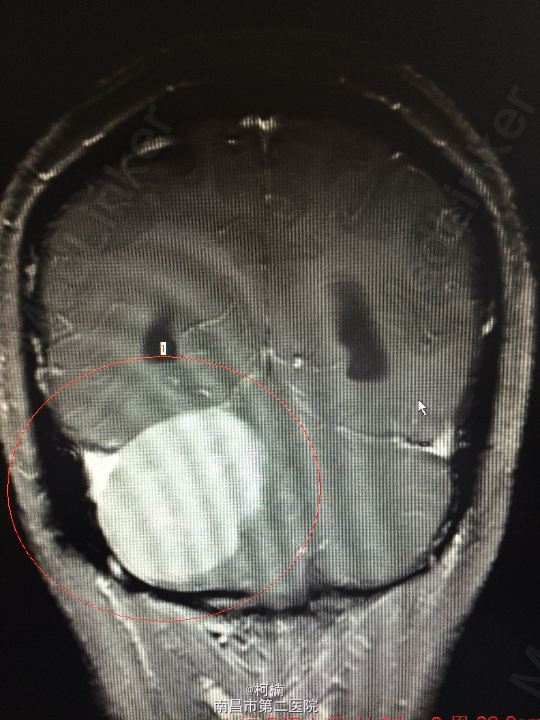

主诉:反复头晕、头痛伴呕吐及行走不稳10月余 病史:患者老年女性,55岁,10余月前开始出现头晕、头痛伴呕吐及行走不稳,无肢体乏力、肢体抽搐、意识障碍等不适,于当地医院诊治行头颅MR提示:右侧小脑角占位,考虑肿瘤。 查体:神经系统体查未见明显异常

查体:神经系统体查未见明显异常 辅助检查:头颅MR提示右侧桥小脑区占位性病变,考虑脑膜瘤。四脑室狭窄,变形,幕上脑室积水,小脑扁桃体疝

诊断:右侧小脑脑膜瘤 处理:先行介入栓塞肿瘤供血动脉,再行开颅手术治疗,术后予组织病理检查,提示:脑膜瘤